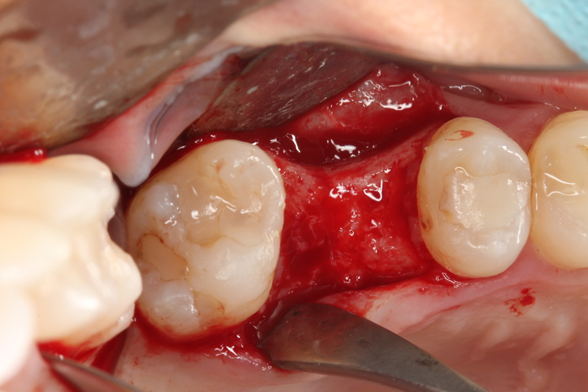

Paciente C.B.F.J., 33 anos, leucoderma, não-fumante e em boas condições de saúde sistêmica, relatou sensibilidade dolorosa durante mastigação no elemento 26, que já possuía tratamento endodôntico, pinos metálicos intrarradiculares e coroa metalocerâmica (Figura 1). Foi solicitada tomografia computadorizada de feixe cônico, na qual a imagem sugeriu fratura radicular na região da furca, descontinuidade óssea da cortical de seio maxilar e opacificação parcial do seio maxilar esquerdo (Figura 2). Foi realizada a exodontia e pôde-se confirmar a comunicação oroantral (Figura 3). Após curetagem do alvéolo, sem preocupação em curetar e remover a lesão cística sinusal, uma barreira reabsorvível foi recortada e posicionada no fundo do alvéolo para obliterar a descontinuidade óssea e impedir que células de tecido mole oriundas da cavidade sinusal invadissem a região alveolar (Figura 4). O alvéolo foi preenchido totalmente por coágulo sanguíneo do paciente (Figura 5) e o alvéolo foi selado por uma barreira não-reabsorvível (Figura 6), impedindo a invasão de fibroblastos do tecido gengival para dentro do alvéolo. Após duas semanas, a barreira estava estável e, então, foi removida, desnudando um tecido de granulação osteoblastogênico (Figura 7).